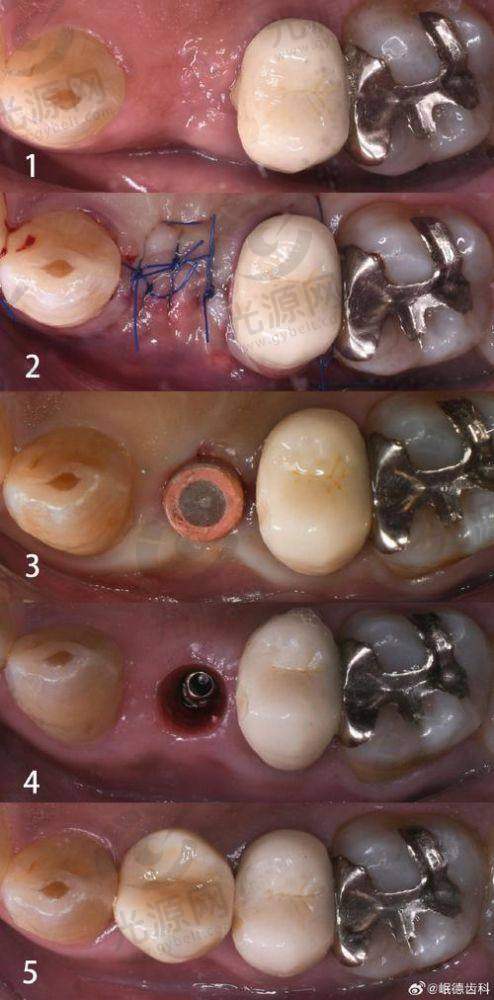

唐山地区的种植牙技术近年来不断更新,尤其是数字化种植技术和微创种植技术逐渐开始普及。这能有效降低患者的手术风险和修复时间,提高成功几率。

实例1:患者李女士在唐山协和口腔医院做了种植牙,选用的是韩国登腾种植体,手术十分顺利,术后也没有明显的肿胀,李女士表示非常满意,咀嚼能力明显提升。